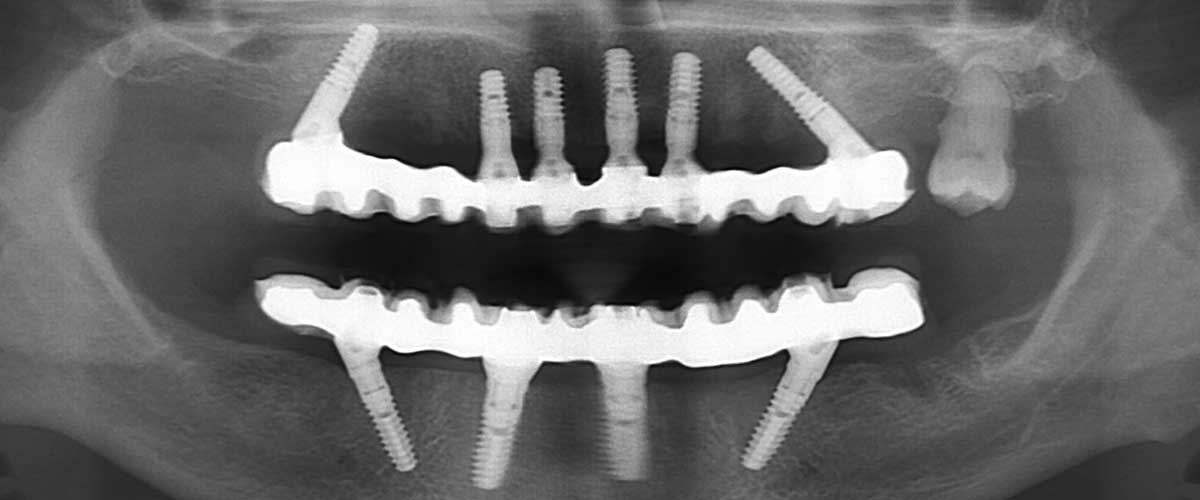

• extracția tuturor dinților determinată de boala parodontală avansată

• Fast&Fixed By Bredent: all on 4 și all on 6